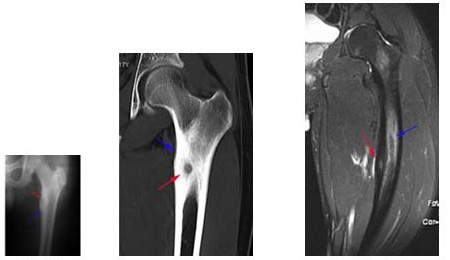

Fig. 1:

(A, B): Osteoid osteoma. Plain radiograph (A) and

CT (B) showing a typical meta-diaphyseal, cortical

osteoid osteoma involving the upper end of the femur.

The nidus is well seen (red arrow) with the surrounding

cortical thickening (blue arrow).

Fig. 2:

Osteoid osteoma. MRI shows the nidus (red arrow) along

with marrow edema (blue arrow).